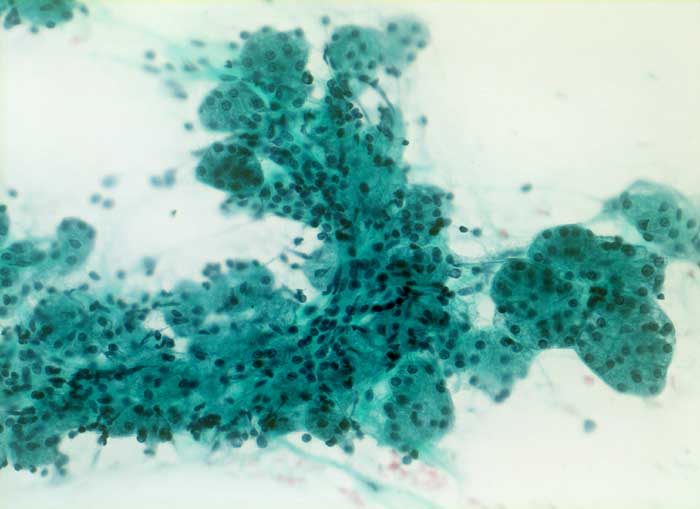

Bei der Sialadenose handelt es sich um eine nicht-entzündliche, nicht-neoplastische diffuse Schwellung der Parotis. Meist sind beide Seiten betroffen. Die Sialadenose kommt vor bei Malnutrition, Alkoholismus, endokrinen Erkrankungen, Diabetes mellitus, neurogenen Erkrankungen oder bestimmten Medikamenten (Antihypertensiva, Sympathomimetika). Die Punktion kann schmerzhaft sein. Die Speicheldrüsenazini messen durchschnittlich 60 bis 75 Mikrometer (Normal: 50 Mikrometer). Typisch sind einzelne sehr grosse Azini von bis zu 100 Mikrometer Durchmesser. Das Zytoplasma der Azinuszellen ist geschwollen und kann degranuliert sein. Eine Neoplasie oder Entzündungszellen sind nicht nachweisbar.